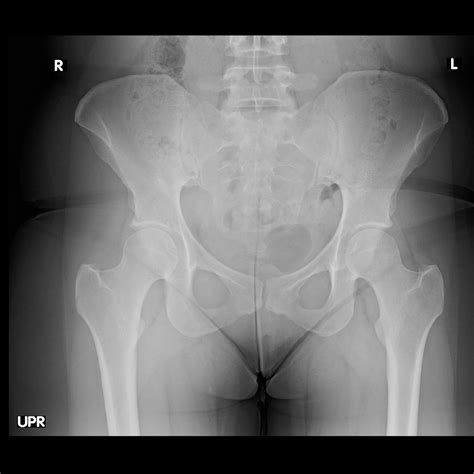

Feb 1, 2024 · Hip labral tear Hip labral tears are more common in people who play certain sports or who have structural problems of the hip. If conservative treatments don't help, a health care provider may. Feb 1, 2024 · Imaging scans A hip labral tear rarely occurs by itself. In most cases, other structures within the hip joint also have injuries. X-rays are excellent at visualizing bone. They can check for. Hip impingement with labral tears or other secondary damage requires prompt treatment. Timely evaluation and diagnosis are critical to alleviate pain and prevent further damage, which can arise if. Feb 5, 2022 · Sports such as soccer, football and golf can increase your risk of damaging the ring of cartilage that helps cushion and stabilize your hip joint. Hip labral tears are more common in people who play certain sports or who have structural problems of the hip. If conservative treatments don't help, a health care provider may suggest surgery to repair.